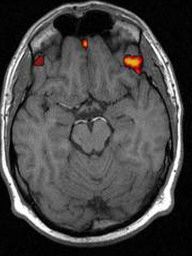

Известно, что современные детекторы лжи неспособны с достаточной точностью определить, лжет человек или нет. Специалисты из Италии предложили использовать новую технологию. Они выяснили, что если наблюдать за определенной частью мозга под названием DLPFC (dorsolateral prefrontal cortex), то с помощью соответствующего оборудования можно выявить намерение человека солгать. По словам исследователей из Миланского университета, эта часть мозга включается в те моменты, когда человек отвергает что-то, что произошло на самом деле. Процедура сканирования безболезненная, уверяют ученые. В ходе ее через голову испытуемого проводят небольшой электрический ток. Это называется tDCS (transcranial direct current stimulation). Данная технология уже используется для стимуляции работы мозга, сообщает ANSA. Источник: http://zhelezyaka.com | Фестиваль итальянской кухни «Еда как искусство» (Il cibo come arte) стартовал в МосквеФестиваль итальянской кухни «Еда как искусство» (Il cibo come arte) пройдет в столице с 1 по 10 апреля в рамках года туризма Италии в России. Во время фестиваля поклонников итальянской кухни и профессионалов кулинарного дела ждет немало увлекательных гастрономических событий и мастер-классов ![]() КУХНЯ |